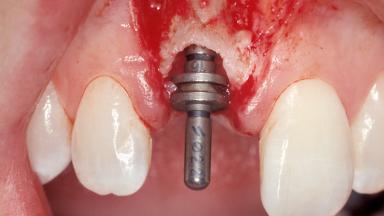

A 30-year-old female patient was referred to the office for the treatment of tooth 11. Her chief concern at the initial visit was to inquire, “Why is my tooth pink?” Upon clinical examination, it was determined that tooth 11 had a previous history of trauma and that the clinical crown had become noticeably pink in color as a result of internal resorption. This diagnosis was confirmed radiographically, indicating a large radiolucency involving the central and distal portions of the clinical crown. It was determined that restoration of this tooth was not possible, and that extraction was indicated. The presence of a mid-line diastema, which the patient wanted to reproduce, directed the treatment plan for tooth replacement utilizing a dental implant.

Placement Protocol | Immediate implant placement |

Tooth Site | Maxillary incisor or canine |

Socket Morphology | Single-root socket |

Socket Integrity | Sufficient, with intact bone walls |

Bone Volume | Sufficient, with intact walls |